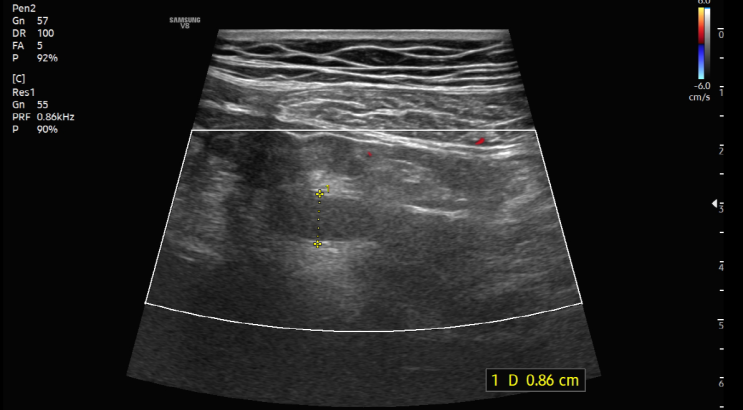

[황학동 복부초음파]서울으뜸내과, 복통으로 진단된 요로결석

#서울으뜸내과 #황학동내과 #왕십리내과 #왕십리복부초음파 #상왕십리복부초음파 #왕십리신장초음파 안녕하...